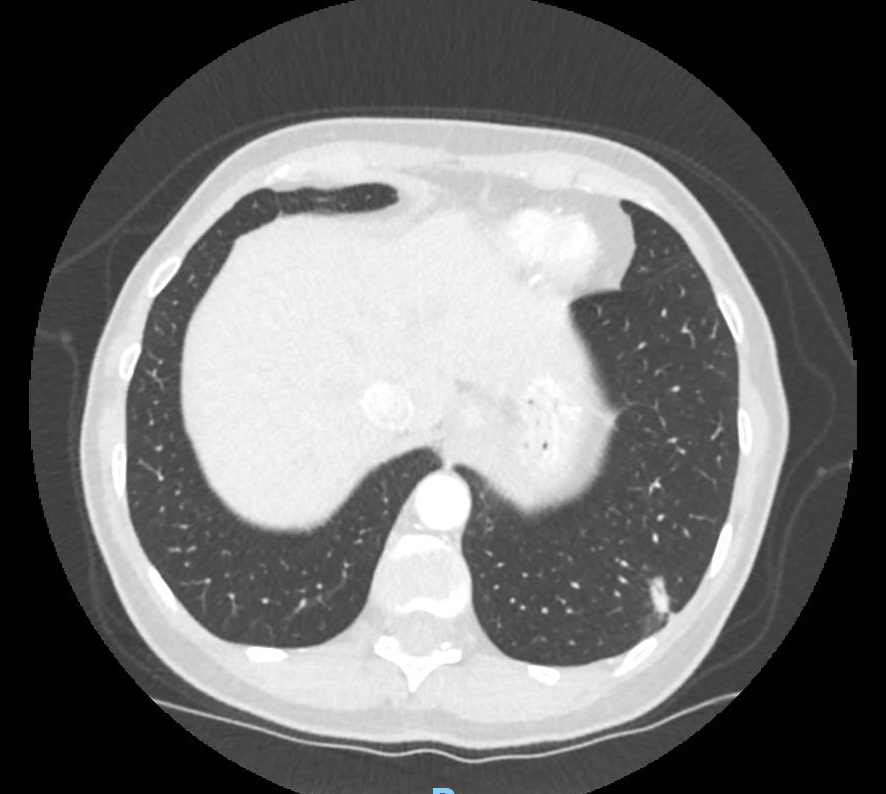

A 62-year-old woman, active smoker, presented with an episode of mild hemoptysis. A chest CT scan revealed a mediastinal adenopathy/mass on station 5 (ATS lymph node classification), located between the aorta and the left pulmonary artery.

PET/CT scan was positive on the lymph node. Given these findings, she underwent a linear endobronchial ultrasound (L-EBUS) under conscious sedation (midazolam + fentanyl).

EBUS-guided transbronchial needle biopsy (TBNB) was performed using a 22G Franseen needle tip (Acquire Pulmonary) with slow-pull technique.

Small Cell Lung Cancer (SCLC).